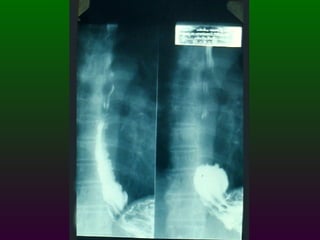

SEGD PATOLOGÍA  ESOFÁGICA A.- Estrechamientos y dilataciones secundarias Acalasia Estenosis Esclerodermia Enf. de Chagas Neoplasia Lesiones por quemadura (cáusticos y dietéticos etc.)